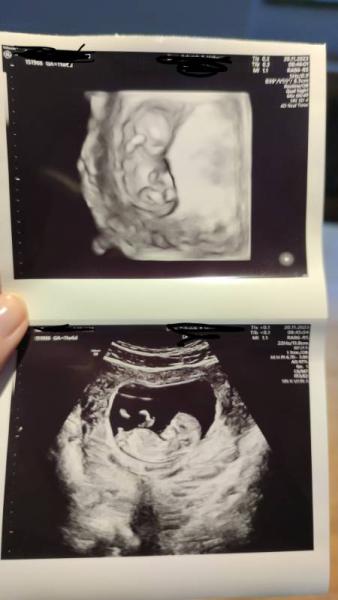

Ich hatte heute meinen 2. Termin, außerdem haben wir die BA für den Harmonytest, CMV & Ringelröteln gemacht. Unserem Böhnchen geht's gut, knapp 5cm gross ist es schon. Hinterwandsplatzenta und bisher gut entwickelt. Morgen bin ich schon 12+0, die Zeit rennt. Diese Schwangerschaft läuft viel mehr nebenher, es weiss auch noch kaum einer. Sonst geht es mir viel besser, Geruchsempfindlich bin ich noch aber der Hunger ist wieder mehr da :) Schönen Montag euch

Bild zu 2. Termin & Harmony Test - Forum für Juni - Mamis